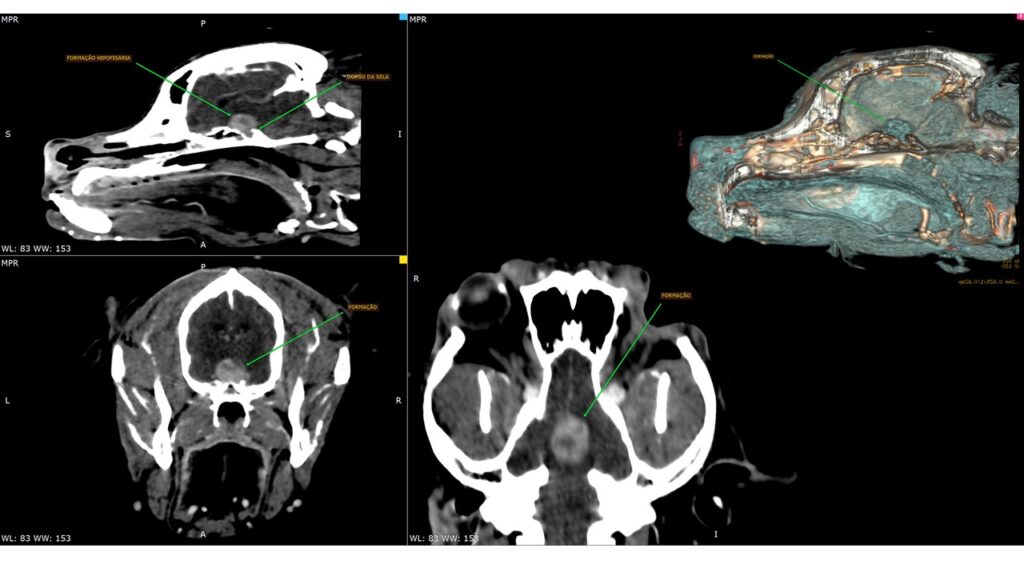

A tomografia computadorizada (TC) de crânio é uma ferramenta de diagnóstico por imagem amplamente utilizada na avaliação de convulsões em cães e gatos. Esse exame permite uma análise detalhada das estruturas encefálicas, ajudando a detectar condições que possam estar causando os episódios convulsivos.

- Detecção de lesões ósseas e encefálicas: como hidrocefalia, tumores, áreas de hemorragia, necrose ou inflamação.

- Avaliação pós-administração de contraste: que pode evidenciar formações tumorais, inflamações e outras anormalidades de forma mais detalhada.